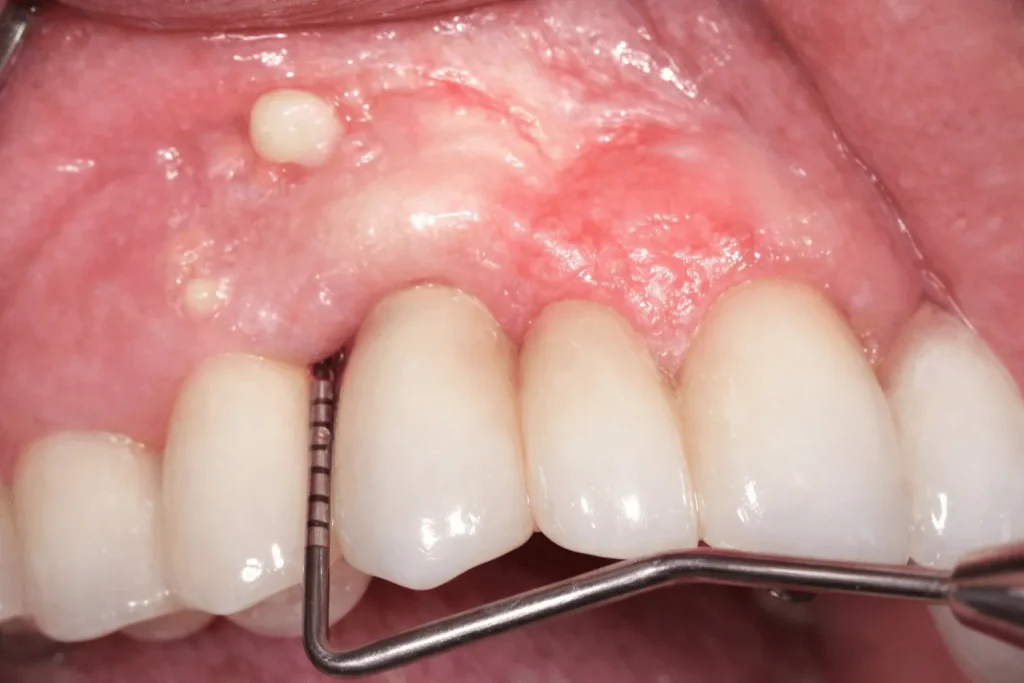

تفاوت التهاب لثه بعد از ایمپلنت با آبسه ایمپلنت

ممکن است شباهتی میان علائم و دلایل التهاب لثه و آبسه ایمپلنت وجود داشته باشد. برای اینکه بتوان این دو را از یکدیگر متمایز کرد، باید ویژگیهای هر کدام را به طور جداگانه بررسی کرد. در جدول پیشرو به بررسی تفاوتهای التهاب لثه و آبسه ایمپلنت خواهیم پرداخت.

| ویژگی | آبسه ایمپلنت | التهاب لثه |

|---|---|---|

| درمان | نیاز به مراجعه به متخصص | معمولا در خانه درمان میشود |

| چه زمانی بروز میکند؟ | در هر زمان امکان دارد؛ بعد از جراحی یا ماهها بعد از جراحی | از ۷ روز بعد از جراحی |

| میزان درد | شدید و کوبشی | خفیف تا متوسط |

| چرک | دارد | ندارد |